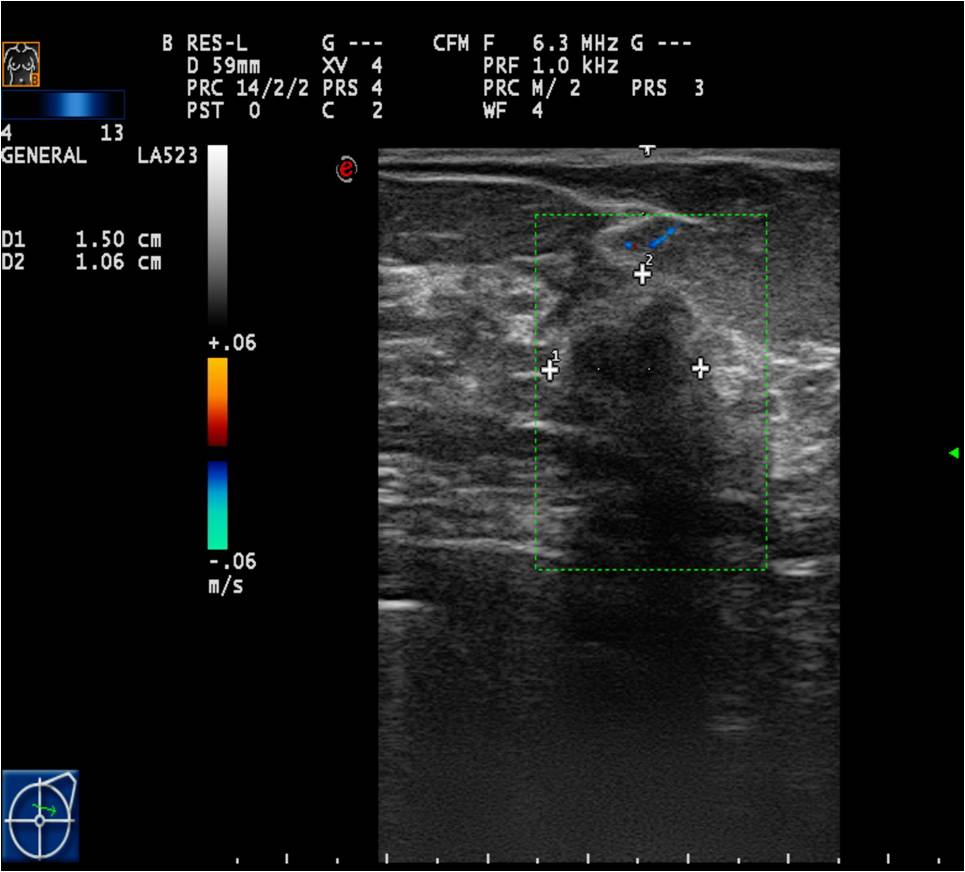

Doppler examinations: can only be used as auxiliary exams. It depicts higher vascularization in malignant tissues.

Elastrography: hard, not compressible lesions in the breast are suspicious for malignancy

Ultrasonography can help in their differentiation; can depict anechoic cystic lesions (Picture17.) or solid masses (Picture 18.). These lesions usually each have a smooth, sharp edge and echo-enhancement can appear behind them. Rarely, cysts contain tumors. (Picture19.).

Ill-defined margins, with uneven contours and blurred edges are usually characteristic of malignant lesions. During ultrasound examination echo-attenuation occurs frequently behind these inhomogeneous hypo-echogenic masses (Picture 20).